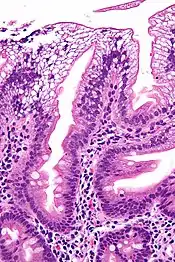

| Micrograph showing enterocytes with a clear cytoplasm (due to lipid accumulation) characteristic of abetalipoproteinemia. Duodenal biopsy. H&E stain. | |

There is an absence of apolipoprotein B. On intestinal biopsy, vacuoles containing lipids are seen in enterocytes. This disorder may also result in fat accumulation in the liver (hepatic steatosis). Because the epithelial cells of the bowel lack the ability to place fats into chylomicrons, lipids accumulate at the surface of the cell, crowding the functions that are necessary for proper absorption.